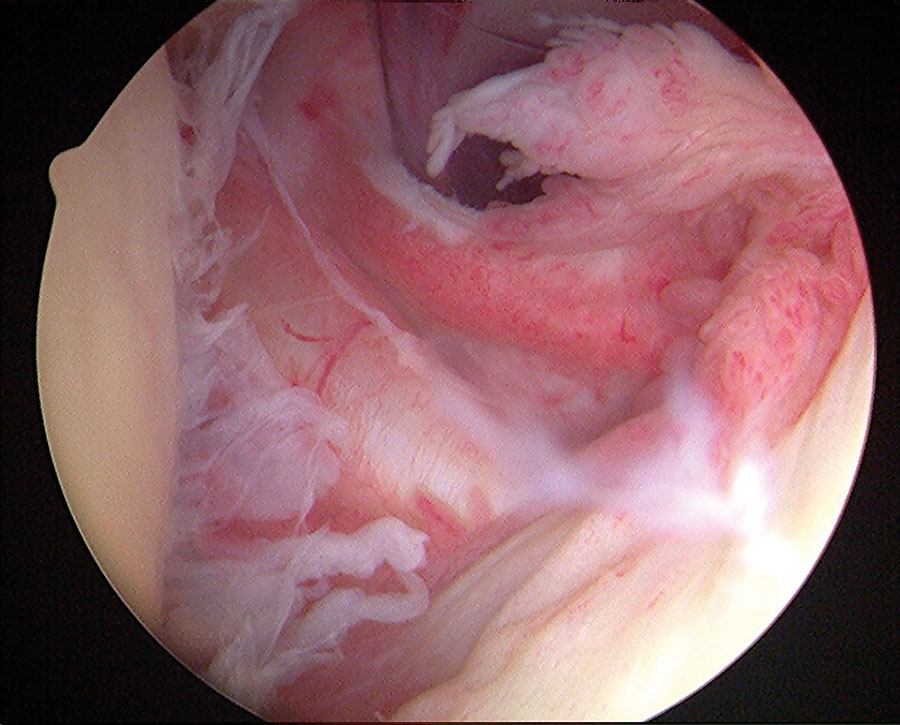

粘连性囊炎(AC),或冻肩,只是一系列影响肩关节的常见疾病之一,其在普通人群中的患病率约为2%。这种疾病表现为肩关节的球窝关节(盂肱关节)僵硬、疼痛和功能障碍。通常伴有周围肌腱套肌肉的问题。交流电在女性和40-60岁人群中最常见。虽然AC通常是自我限制的,可能在一些人两年内解决,它可能导致持续的问题,对许多人,特别是糖尿病患者。

尽管我们对交流电的表现方式有很多了解,但对这种情况的潜在原因却知之甚少。正是这一点,理查德·佩奇教授和斯蒂芬·吉尔博士希望能了解得更多。粘连性囊炎与肩袖病、一些其他内分泌疾病和创伤有关,提示发病机制中存在代谢或炎症共同途径。事实上,有人认为继发性AC可能与创伤或手术史、心脏病发作或糖尿病有关。糖尿病的患病率高达38.6%,AC是与糖尿病相关的最常见的关节疾病。

作为这项工作的一部分,正在收集关节置换感染的组织和血液样本,目的是改善未来患者感染的早期诊断。这种生物库工作也可能产生潜在的生物标志物,可以改善具有挑战性的关节置换术感染的诊断和管理。研究人员正在使用这个组织库平台来调查一系列的情况,包括骨关节炎、关节不稳定、肌腱和肩袖疾病、冰冻肩膀和关节置换感染。除了探索这种疾病本身,佩奇教授还对影响患者的系统性代谢疾病(如糖尿病)的联系感兴趣。